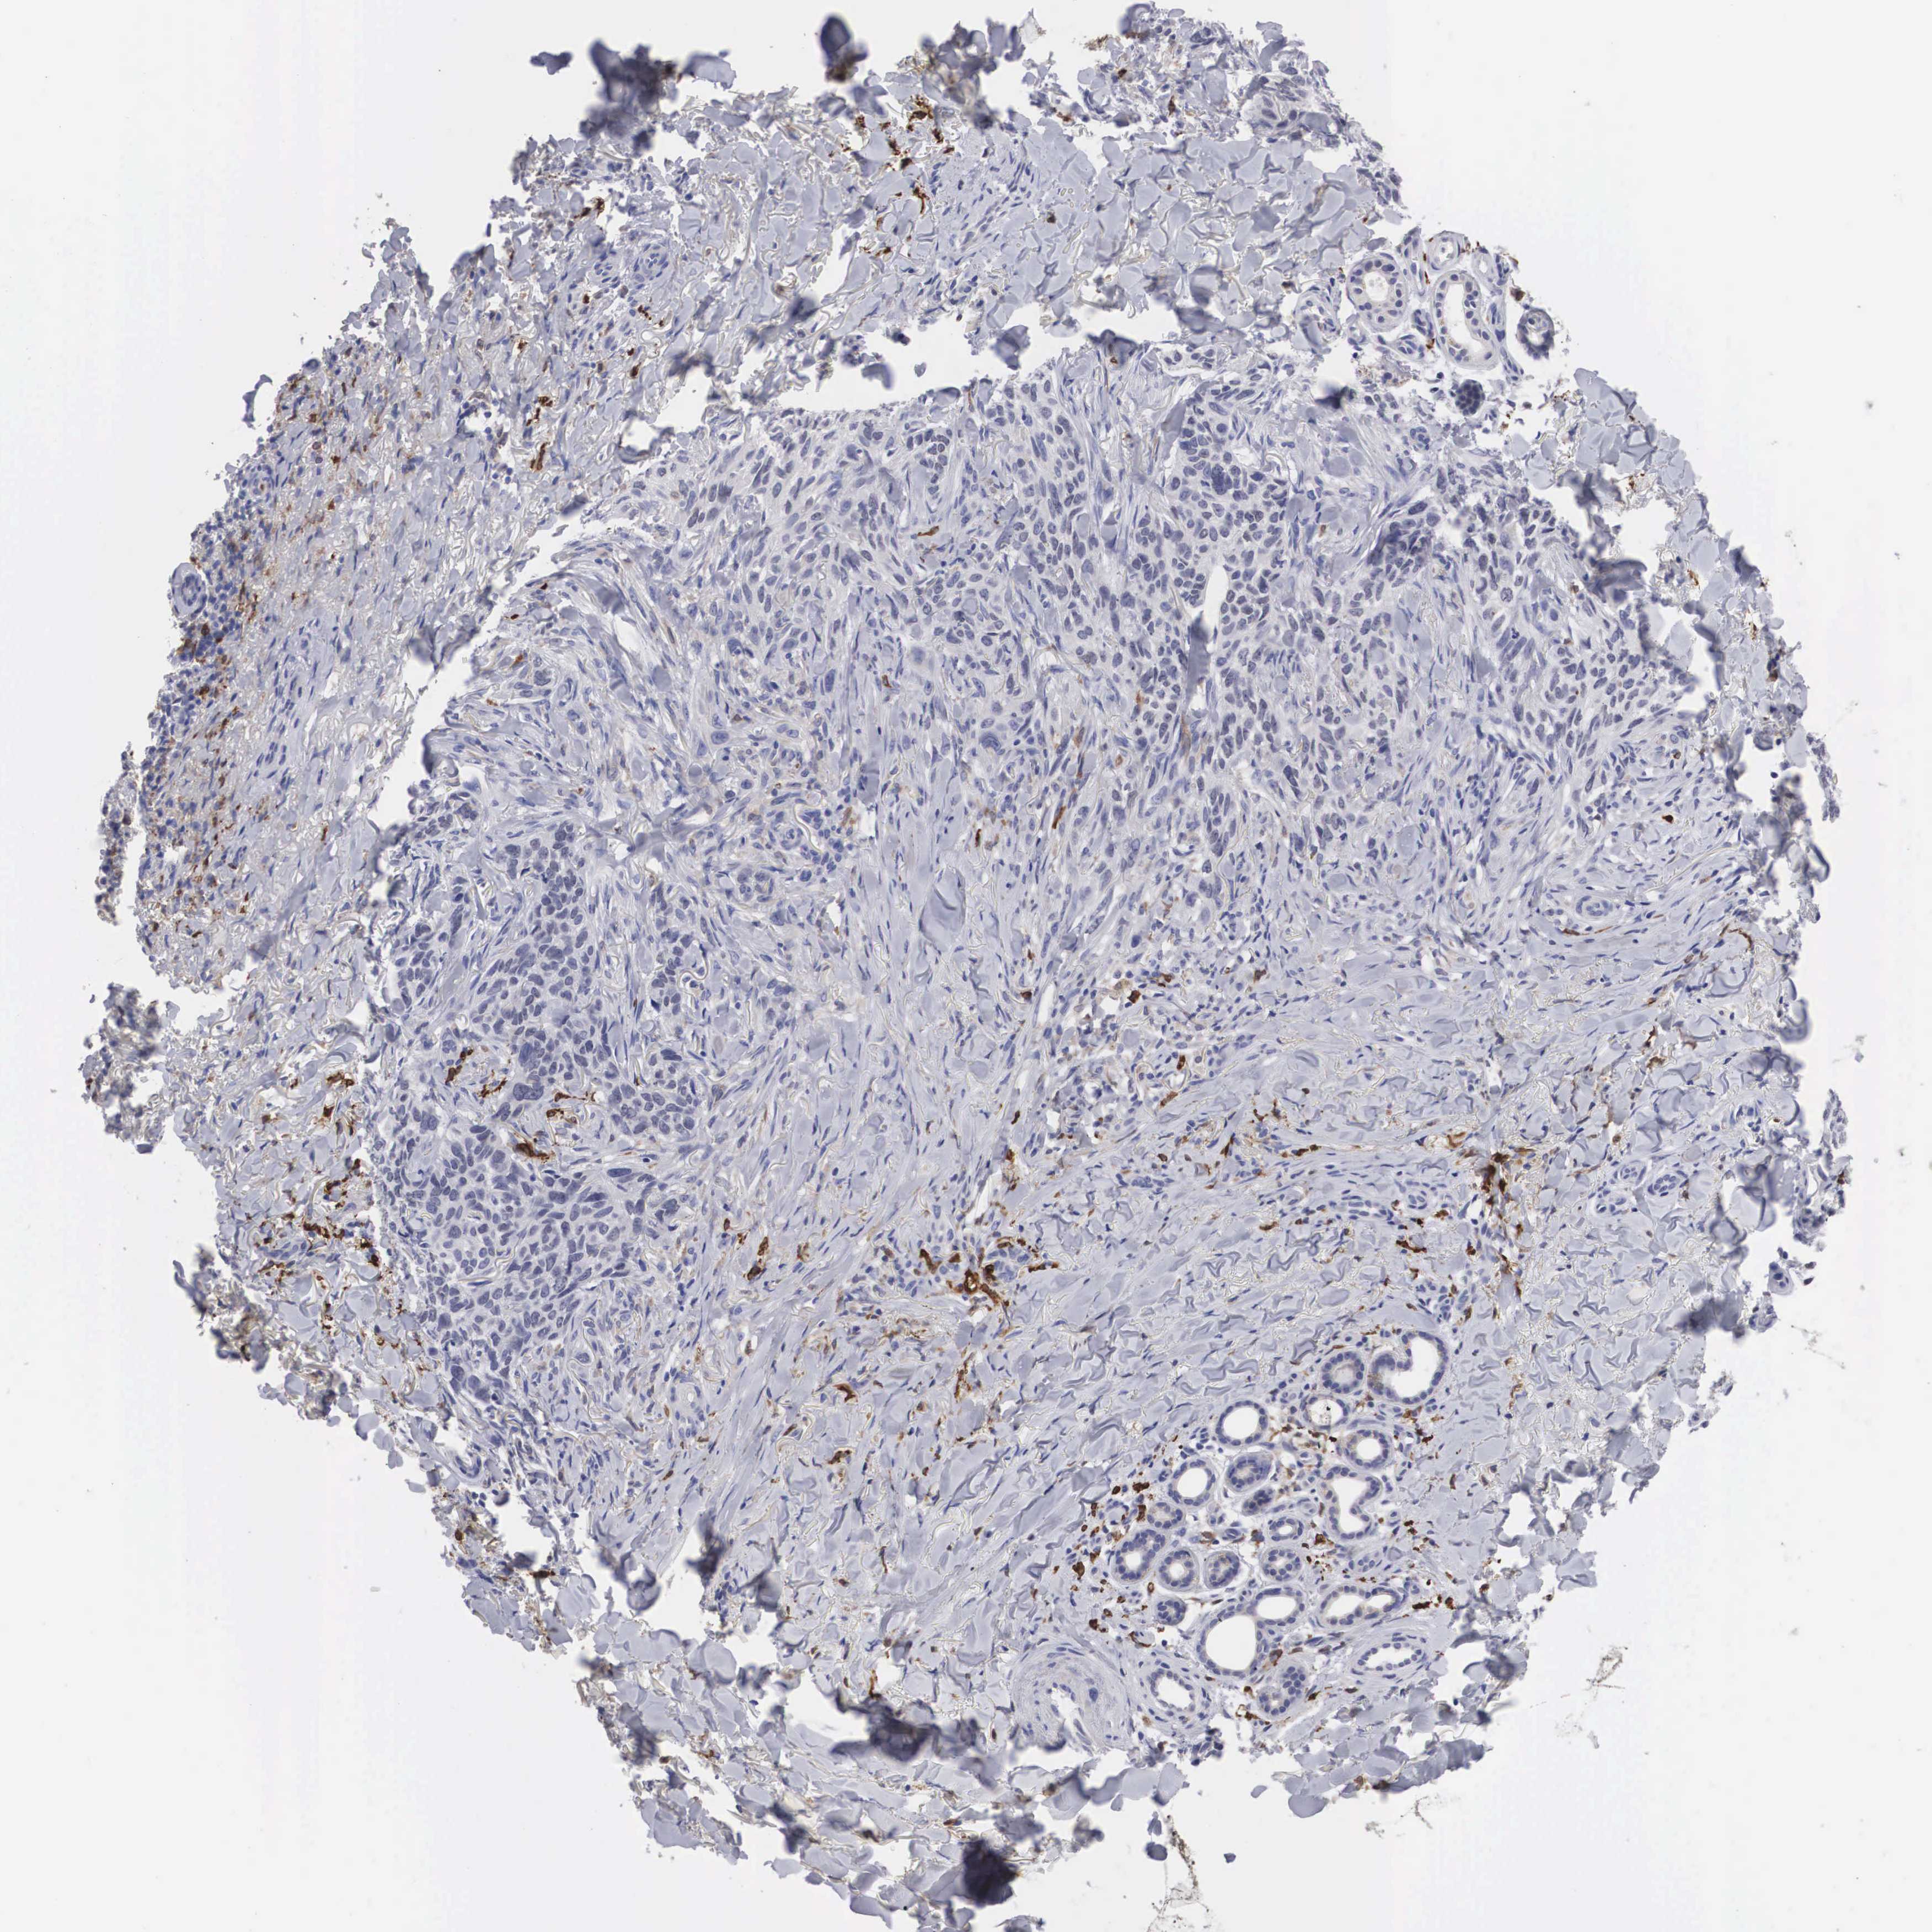

Basal cell and squamous cell cancer

SKIN CANCER - Protein expressioni

A mouse-over function shows sample information and annotation data. Click on an image to view it in a full screen mode. Samples can be filtered based on level of antibody staining by selecting one or several of the following categories: high, medium, low and not detected. The assay and annotation is described here.

Antibody stainingi

Antibody staining in the annotated cell types in the current human tissue is reported as not detected, low, medium, or high, based on conventional immunohistochemistry profiling in selected tissues. This score is based on the combination of the staining intensity and fraction of stained cells.

Each image is clickable and will lead to virtual microscopy that enables deeper exploration of all samples and also displays staining intensity scores, fraction scores and subcellular localization as well as patient and tissue information for each sample.

Antibody HPA000635

Antibody CAB017444

Squamous cell carcinoma, NOS